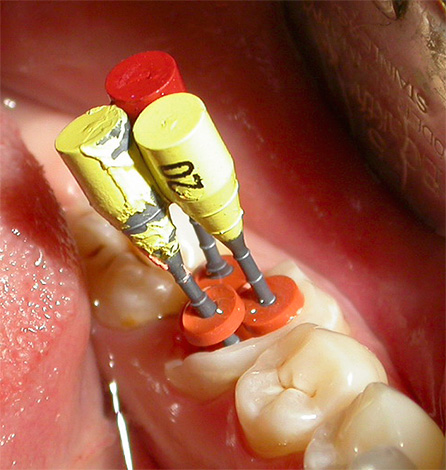

Le foto seguenti mostrano come appaiono alcune fasi della depulpazione dei denti (rimozione del nervo):

L'immagine mostra cosa succede quando la carie raggiunge la polpa e porta alla sua infiammazione: